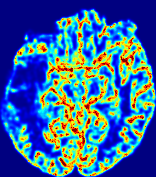

Slice #1Slice #2Slice #3Slice #4Slice #5Slice #6Dgtsuperscript𝐷gtD^{\text{gt}}Refer to captionRefer to captionRefer to captionRefer to captionRefer to captionRefer to captionDestsuperscript𝐷estD^{\text{est}}Refer to captionRefer to captionRefer to captionRefer to captionRefer to captionRefer to captionRefer to caption0.300.300.300.240.240.240.180.180.180.120.120.120.060.060.060.000.000.00(mm2/s)𝑚superscript𝑚2𝑠(mm^{2}/s)𝐕est𝟐subscriptnormsuperscript𝐕est2\|\bf{V}^{\text{est}}\|_{2}Refer to captionRefer to captionRefer to captionRefer to captionRefer to captionRefer to captionRefer to caption0.00300.00300.00300.00240.00240.00240.00180.00180.00180.00120.00120.00120.00060.00060.00060.00000.00000.0000(mm/s)𝑚𝑚𝑠(mm/s)

Figure 15: PIANO identifiability testing: diffusion imaging via advection-diffusion. Top row shows Dgtsuperscript𝐷gtD^{\text{gt}} used for simulating ground truth pure diffusion. Rows below show the estimated Destsuperscript𝐷estD^{\text{est}} and 𝐕est2subscriptnormsuperscript𝐕est2\|{\bf{V}}^{\text{est}}\|_{2} on corresponding slices. Note that the plotted value scale for 𝐕est2subscriptnormsuperscript𝐕est2\|{\bf{V}}^{\text{est}}\|_{2} is 0.01 of that for Dgtsuperscript𝐷gtD^{\text{gt}} and Destsuperscript𝐷estD^{\text{est}}.

Similarly, we test the behavior of PIANO when estimating both advection and diffusion from a pure diffusion-driven process. The goal is to determine if PIANO is able to recognize that there is only diffusion governing the given concentration time-series. We use the same ‘Diffusion Imaging’ data simulation of Sec. 4.2.1 as the concentration dataset, PIANO estimates both velocity 𝐕estsuperscript𝐕est{\bf{V}}^{\text{est}} and diffusivity Destsuperscript𝐷estD^{\text{est}}. Estimation results in Fig. 15 confirm PIANO’s identifiability again: the estimated 𝐕est2subscriptnormsuperscript𝐕est2\|{\bf{V}}^{\text{est}}\|_{2} is almost invisible compared to Destsuperscript𝐷estD^{\text{est}}, even plotted with a 1%percent11\% value range compared to that for Destsuperscript𝐷estD^{\text{est}}. On the other hand, Destsuperscript𝐷estD^{\text{est}} achieves comparable estimation performance as ‘Diffusion Imaging via Diffusion’ in which PIANO predicts Destsuperscript𝐷estD^{\text{est}} alone (shown in Fig. 13).